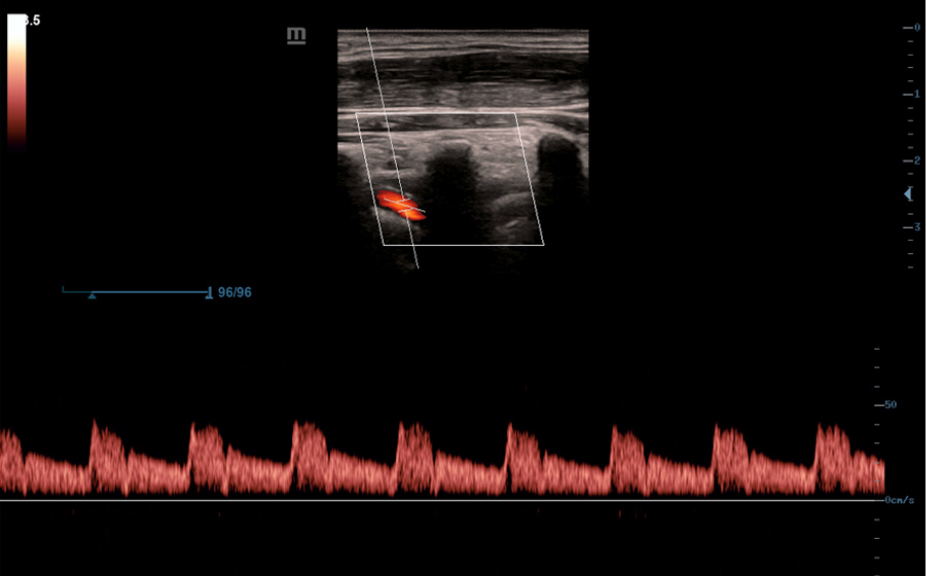

Sistema de diagnĂłstico ecogrĂĄfico

DC- 30

AtenciĂłn primaria con una excelente visiĂłn

FullHD

ImĂĄgenes clĂnicas